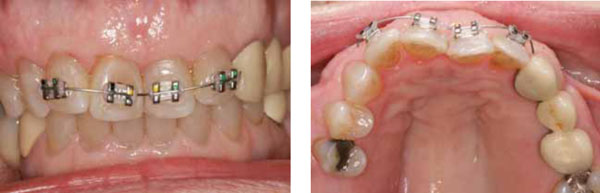

View after composite restorations but before orthodontic repositioning. The teeth were still rotated in toward the tongue at the midline as a result of the fall.

Orthodontic therapy involved .014-inch NiTi wire (shown) and .018 x .025-inch NiTi (not shown).

On January 24, 2013, orthodontic brackets were placed on her teeth, and we started a program of limited orthodontic treatment that was designed to restore her teeth to their original positions. In other words, the orthodontic treatment was not done for esthetic reasons; it was done primarily to restore her ability to enjoy normal oral function without pain. It was reasoned that if the teeth were restored to their former positions (Class II, Division 1, large overjet), then the lip biting caused by their altered positions would cease. Secondarily, it was considered reasonable to restore her teeth to an esthetic appearance that approximated the way she looked before the incident. In other words, this was not a “Hollywood smile makeover”; it was a good-faith effort to restore her teeth to the condition they were in before the incident—nothing more, nothing less. This was discussed with the patient, who then approved the concept and consented to the specific treatments that were rendered to implement this concept (Figs. 10 and 11).

The goal of orthodontic treatment was to return her teeth to their original pre-trauma positions. No effort was made to correct her Class II malocclusion, which was recognized and discussed but deemed unimportant by the patient. She had always been Class II, she was used to it, and it had not been a problem for her. Therefore, she did not wish to undertake any correction of that condition, and we were able to accommodate her preference in good faith. NiTi round wire (.012-inch) followed by NiTi heat-activated wire (.018 × .025-inch) in fixed metal (.022-inch) brackets was used to reposition the incisors (Figs. 11 and 12). The arch form was restored to a close approximation of the form that it had enjoyed prior to the incident. This correction enabled the patient to resume normal function by eliminating the protrusive interference and the lip biting problem. Examination of post treatment study casts shows overjet restored to original condition (Fig. 13). The comfort and restoration of normal function finally enabled the patient to smile again (Fig. 14).